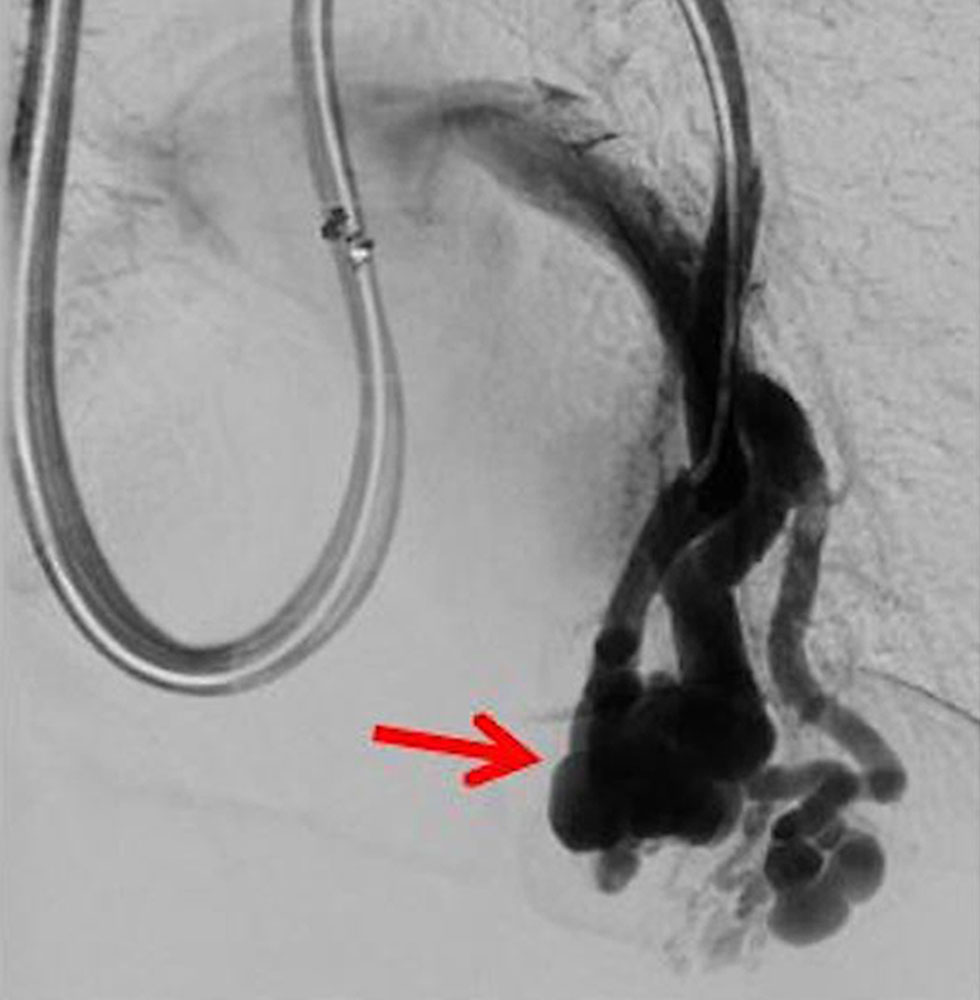

Venous malformations, in particular, often extend to the ipsilateral scrotum in male patients, and somewhat less frequently to the penis. Even if more extensive, this is usually not very symptomatic in men and more cosmetically noticeable. Sexual function and fertility in men is not disturbed in most of these cases since the changes are usually epifascial and surround but do not involve the testis. An invasive therapy (sclerotherapy) is rarely necessary, but it is certainly possible and successful.